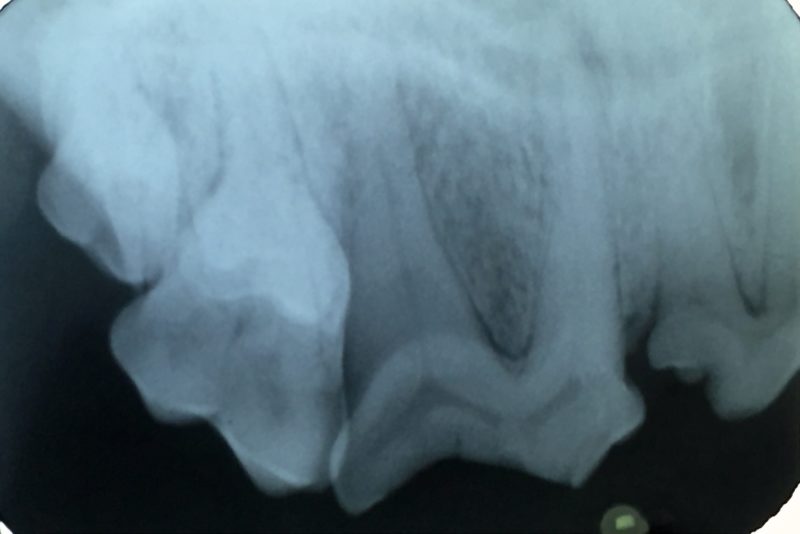

Vor der geplanten Operation brauchten wir jedoch noch einige Tropfen von Lottes Blut für eine Blutuntersuchung. Damit wollten wir weitere Erkrankungen ausschließen und das Narkoserisiko der bereits älteren Patientin (14 Jahre) minimieren. Im hauseigenen Labor haben wir die Leber- und Nierenwerte überprüft. Es lagen keine Veränderungen der Blutwerte vor, und so konnten wir mit der Operation noch am gleichen Tag beginnen. Nach Einleitung der Narkose fertigten wir zunächst ein Dentalröntgenbild des betroffenen Zahnes an, um das Ausmaß der Entzündung zu erkennen und weitere Frakturen in der Tiefe ausschließen zu können (Foto 4). Der Reißzahn ist der größte Backenzahn im Hundemaul und hat im Oberkiefer drei Wurzeln, darüber hinaus im Unterkiefer zwei. Funktionell sind diese beiden Zähne beim Zerkleinern des Futters am wichtigsten. Daher streben wir Tierzahnärzte immer an, sie zu erhalten und eine Wurzelkanalbehandlung mit anschließender Füllung durchzuführen.

Bei „Lotte“ lag jedoch eine komplizierte Fraktur mit gespaltener Krone vor, so dass tatsächlich nur eine Extraktion des Zahnes in Frage kam. Solch ein dreiwurzeliger Zahn kann nicht im Ganzen gezogen werden. Die Wurzeln sitzen fest im Kiefer und sind gerade bei schon älteren infizierten Zähnen sehr spröde und morsch und brechen leicht in der Tiefe ab. Daher ist eine kieferchirurgische, offene Extraktion die Methode der Wahl. So wurde bei „Lotte“ die Mundschleimhaut um den Zahn herum gelöst und der Kieferknochen freigelegt. Dann wurde der Knochen mit einem wassergekühlten Bohrer über den Zahnwurzeln entfernt, bis diese komplett sichtbar waren. Anschließend wurde der Zahn mit einem Fräser in drei Teile geteilt und die einzelnen Wurzeln mit verschiedenen Hebeln gelockert, um sie danach separat ziehen zu können (Foto 2). Besonders wichtig ist es, dass keine Wurzelreste im Kiefer verbleiben, denn diese verursachen weiterhin Schmerzen und führen zu einer Abszessbildung im Kieferknochen. Nach Glättung der scharfen Knochenkanten wurde die Schleimhaut wieder über die Wunde gelegt und mit einer Wundnaht mit Einzelheften eines resorbierbaren Nahtmaterials verschlossen, welches sich nach einigen Wochen von selbst auflöst (Foto 3).